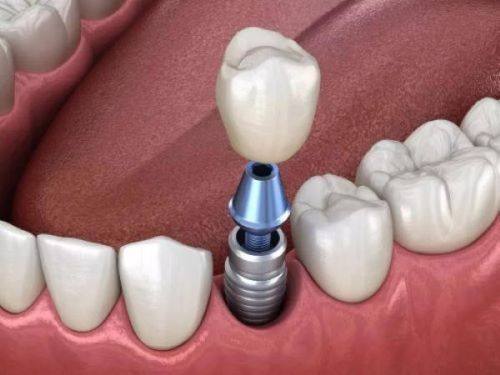

种牙打桩后的修复过程

种牙打桩后的修复过程可以分为几个阶段。在手术后的当天,伤口会有轻微的疼痛和肿胀,这是正常的生理反应。患者需要按照医生的嘱咐,咬紧止血棉球,一般30 - 40分钟后可以取出。

到了术后7 - 10天,如果伤口愈合良好,就可以进行拆线。拆线后,伤口还需要一段时间来完全修复,此时仍要注意口腔卫生。